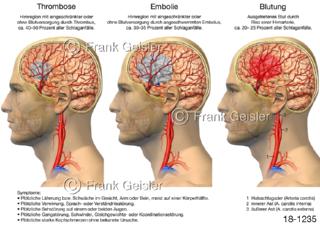

18-1235 Schlaganfall Apoplex, Schlaganfallformen Thrombose Embolie Blutung